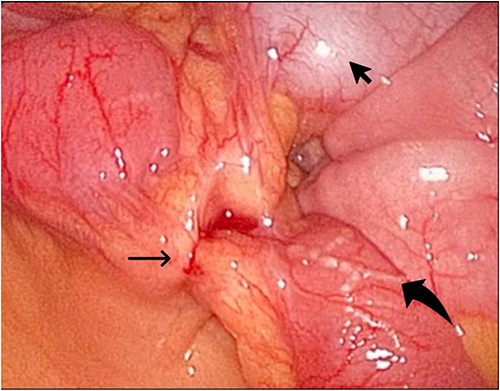

During her hospital stay, the patient showed no improvement regarding abdominal pain, nausea, or abdominal exam. Therefore, she was offered a laparoscopic exploration to verify the diagnosis of a FB to which she agreed. She was taken to the operating room, and the exploration showed an inflammatory process in the LLQ (Fig. 3) with the sigmoid colon attached to the area of the inflammatory reaction. A FB was found in the mesentery of two loops of the ileum 100 cm from the ileocecal junction (Figs 4 and 5). Removal of the FB safely and milking of the small bowel showed no leakage of bowel contents (Fig. 6). And, exploring the rest of the abdomen showed no other pathology and normal ovaries (Figs 7 and 8); the procedure was uneventful. The FB was identified as a toothpick, 3 cm in length (Fig. 9).

The laparoscopic exploration showed the sigmoid colon attached to the area of the inflammatory reaction; straight arrow: site of the toothpick; curved arrow: site of toothpick erosion through the bowel wall; arrowhead: sigmoid colon.